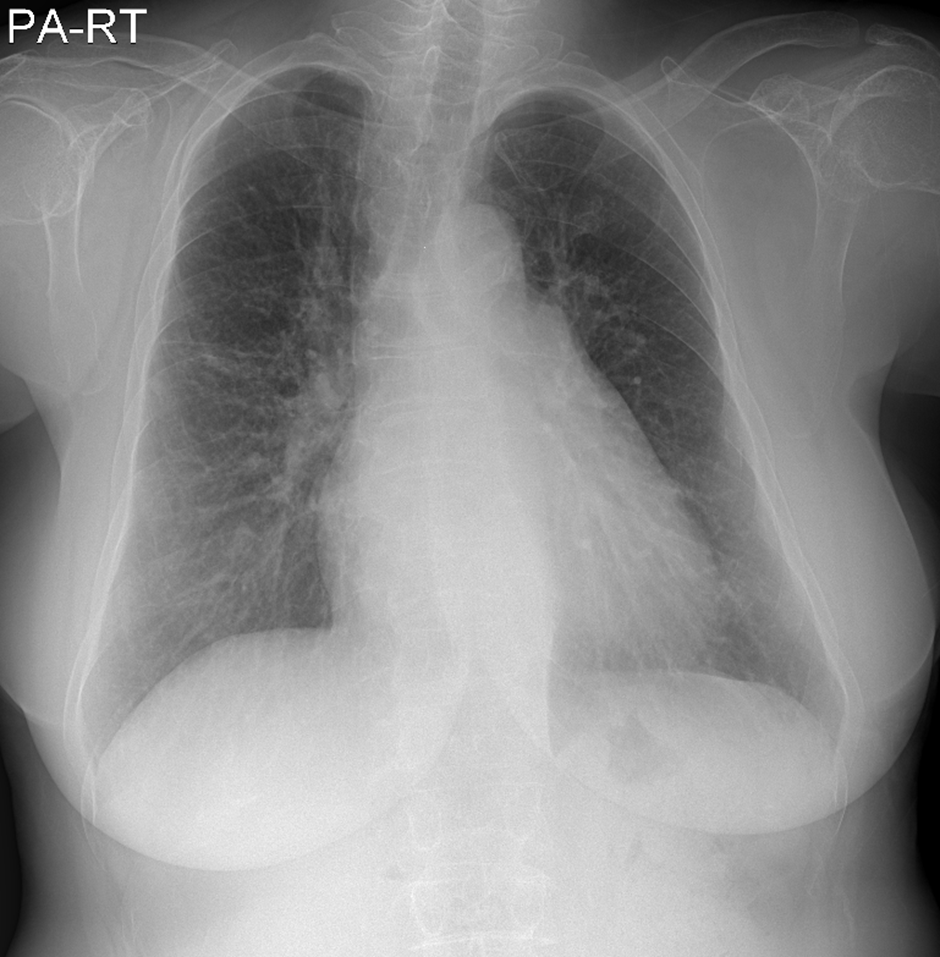

* CXR °ú  chest CT  »çÁøÀÔ´Ï´Ù.

¶Ñ·ÇÇÑ ¿µ»óÀ» À§ÇØ f/u Áß¿¡ ÂïÀº »çÁøÀ» ÷ºÎÇÏ¿´½À´Ï´Ù.

l  Chest CT

Progression of multiple small nodules in both lungs, along peri-BV and ILS, dominant on RUL and RML. No significant change of several small LNs in both hilar and mediastinum.   COPD: diffuse bronchitis. LH enlarge and PAH.